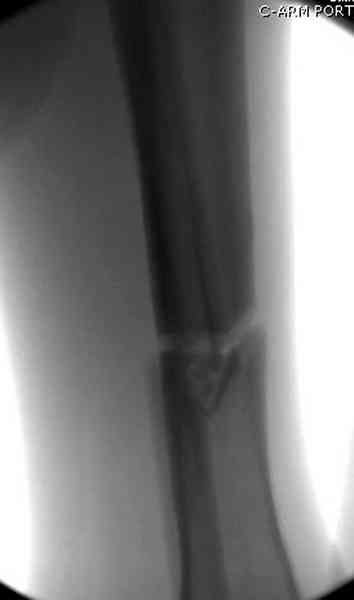

Больному с политравмой установлен наружный "spanning-bridging" фиксатор, после нескольких Irrigation&Debridment на фоне отрицательного посева из раны, через открытый участок установлен 4.5 mm Locking Plate.

На фоне фиксированного перелома бедра мероприятия по восстановлению мягкотканого покрова. Перелом голени зафиксирован после стабилизации бедра традиционным методом.